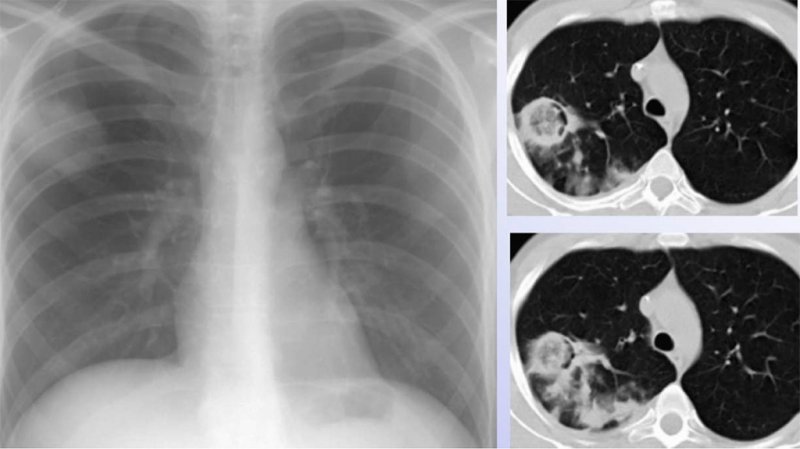

Визуализация и диагностика неинвазивного аспергиллеза с помощью КТ

Раздел: Необычные решения